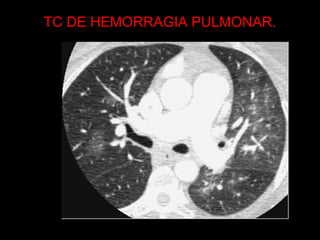

TC DE HEMORRAGIA PULMONAR.

HEMORRAGIA PULMONAR  Podeocorrer por : traumatismos, diátese hemorrágica, aspergilose invasiva, pseudomonas, gripe, drogas, embolia, SDRA, doenças auto-imunes .  As radiografias mostram opacidades bilaterais indistinguíveis do edema pulmonar.  Resolução completa ocorre em 2 semanas.  Prognóstico sombrio.